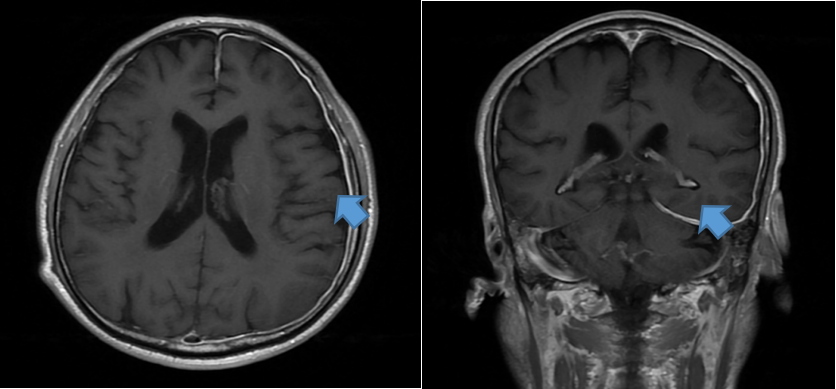

来到我院后,完善实验室检查和腰穿脑脊液检查,提示中枢神经系统感染。进一步完善头颅MRI平扫+增强,左侧额顶颞枕部、小脑幕、部分大脑镰硬脑膜弥漫性强化。诊断为1.肥厚性硬脑膜炎2.中枢神经系统感染3.双侧中耳乳突炎。

(磁共振上可以见到刘先生的硬脑膜增厚如同脑组织穿了“盔甲”一般)